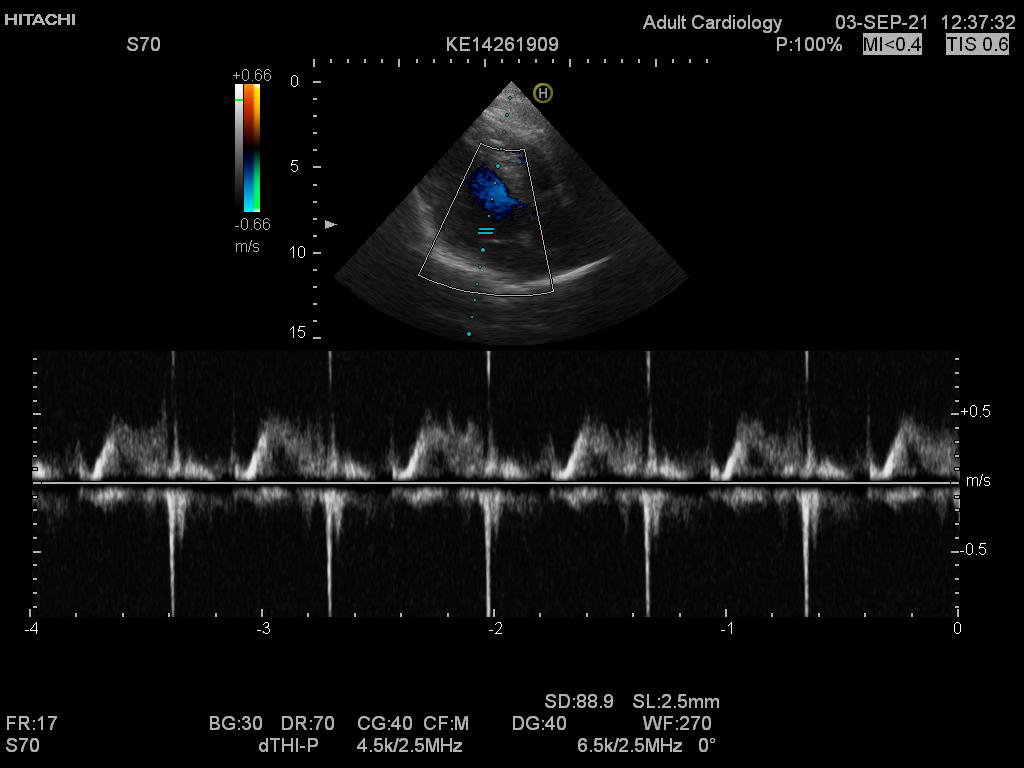

Hitachi EUP-S70 Ref Phased Array – HI VISION

Hitachi Phased Array EUP-S70 Cardio

Intended use

Cardiology and Transcranial

Hitachi EUP-S70 Phased Array – HI VISION

Frequency Range: 5 – 1 MHz

Hitachi EUP-S70 Phased Array – HI VISION for Cardiology and Transcranial

Compatible with Hitachi Hi Vision systems